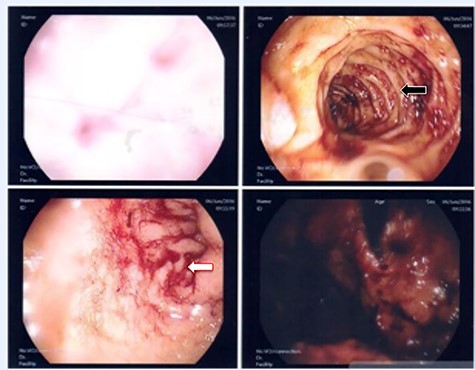

A 36-year-old male, involved in a minor motor vehicle accident while driving his car. He lost consciousness following a sudden onset of transient loss of vision which was not associated with palpitation or dizziness. His previous medical history revealed arterial hypertension and a corrected aortic coarctation with interposition graft at the age of 14. Pan CT scan was unremarkable except for thickening of the desending throacic aorta. His white blood count was very high (68 000 per cubic millimeter of blood). One day after the car accident, he developed nausea, hematemesis and melana. Upper GI endoscopy revealed blood in the stomach and distal esophafgus with no identifiable source of bleeding (Fig. 6). The patient developed massive hematemsis with hypotension requiring intubation and resuscitation. Another CT scan showed air pocket around distal aorta and contrast extravasation to the esophagus (Fig. 7). Another endoscopy revealed distal esophageal ulcer with clot extending toward the stomach (Fig. 8). AEF was suspected and then confirmed by aortogram. The fistula was treated by TEVAR (20 mm × 11.5 cm Valiant covered stent - Medtronic company, USA) followed by fully covered esophageal stent in the middle of the esophagus (Fig. 9).

First upper endoscopy blood within the stomach and duodenum; the esophagus image was not clear and no active bleed can be seen.

Second upper endoscopy fresh bleeding from the distal esophagus and after washing the blood an adherent clot extending from an ulcer going down into the stomach can be seen.